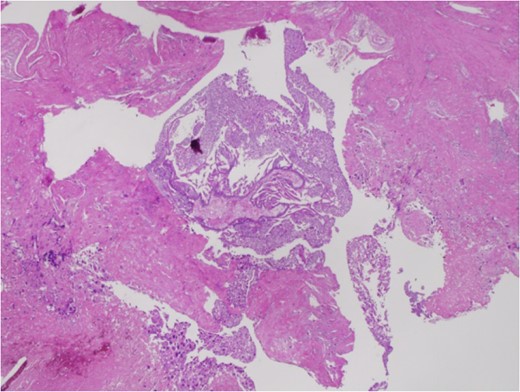

A 50-year-old woman, Gravida 3, Para 1, presented to our department with irregular genital bleeding for 2 months. Her last menstrual period had been 2 months before. Her obstetrical history included a normal vaginal delivery 13 years before and two spontaneous abortions 8 and 11 years previously. Transvaginal ultrasonography showed an enlarged uterus with endometrial thickening with an echogenic pattern (Fig. 1). As endometrial cancer was suspected first, an endometrial biopsy and magnetic resonance imaging (MRI) were performed. The endometrial biopsy revealed decidual tissues, and the MRI revealed invasion of a uterine corpus tumor into the myometrium (Fig. 2). A week later, the patient admitted to the hospital with continuation of irregular vaginal bleeding. Second endometrial biopsy was done and serum β-human chorionic gonadotropin (hCG) level was also measured owing to suspicion of a hydatidiform mole. The serum hCG level was over 225 000 mIU/mL, and the endometrial biopsy revealed a complete hydatidiform mole. Because the patient's hemoglobin level was 7.0 g/dL, owing to the continuation of uterine bleeding, we transfused 800 mL of red cell concentrate and discharged the patient. A lung metastasis, 1 cm in diameter, was observed on a contrast computer tomography scan (Fig. 3), and an invasive mole with lung metastasis was diagnosed. Because the patient did not desire preservation of her uterus or adnexa, we offered her a total abdominal hysterectomy (TAH) and bilateral salpingo-oophorectomy (BSO). At her next consultation for the continuous genital bleeding, a tumor of the right labium minus was recognized and histologically confirmed as a metastatic lesion of the mole (Fig. 4). The patient underwent TAH and BSO. Unfortunately, a tumor of right labium minus had spontaneously fallen off during surgery. In a gross specimen, molar vesicles were recognized at the uterine corpus with the right ovary a little swollen (Fig. 5). The invasions into myometrium by both villi and the trophoblasts were histopathologically confirmed (Fig. 6). In addition to the labium minus tumor, a metastatic lesion of the right ovary was diagnosed. The final pathological diagnosis was metastatic invasive hydatidiform mole, Stage III. The patient's serum hCG level fell to 10 779 mIU/mL after her operation. The patient was then started on administered methotrexate 20 mg/body intramuscularly, 5 days a week at 2 weeks intervals. Serum hCG levels are measured for the estimation of chemotherapy [4]. Her serum hCG level rapidly fell to 1.2 mIU/mL after four courses of methotrexate (Fig. 7). Two additional courses of methotrexate were completed, and there has been no evidence of recurrent disease for 6 months.

Histopathological staining shows the invasions into the myometrium by both the villi and trophoblasts.